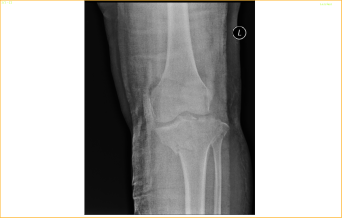

A Tibial plateau fracture with knee joint involvement in a 52-year-old lady!